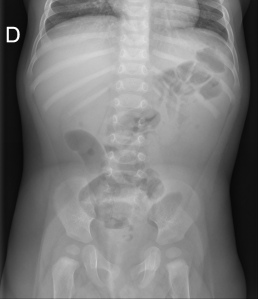

Placa simple: Triada de Rigler: Obstrucción de asas de delgado + gas en el arbol biliar + litiasis (frec en la FID); estos tres hallazgos constituyen la Triada de Rigler.

Tomografía computarizada: S y E del 93% y 100% respectivamente. Hallazgos: Dilatación por obstrucción de asas de delgado. Aerobilia. Litiasis (2 – 3 cm aprox). Hay que tener cuidado ya que muchas litiasis no están calcificadas y su densidad puede ser similar al contenido del intestino. Pueden ser multiples, por tanto hay que poner atención para que no pasen desapercibidas y evitar las recidivas. Fistulas (normalmente entre vesícula y duodeno). Neumoperitoneo (gas portal o gas mural indican peor pronóstico).